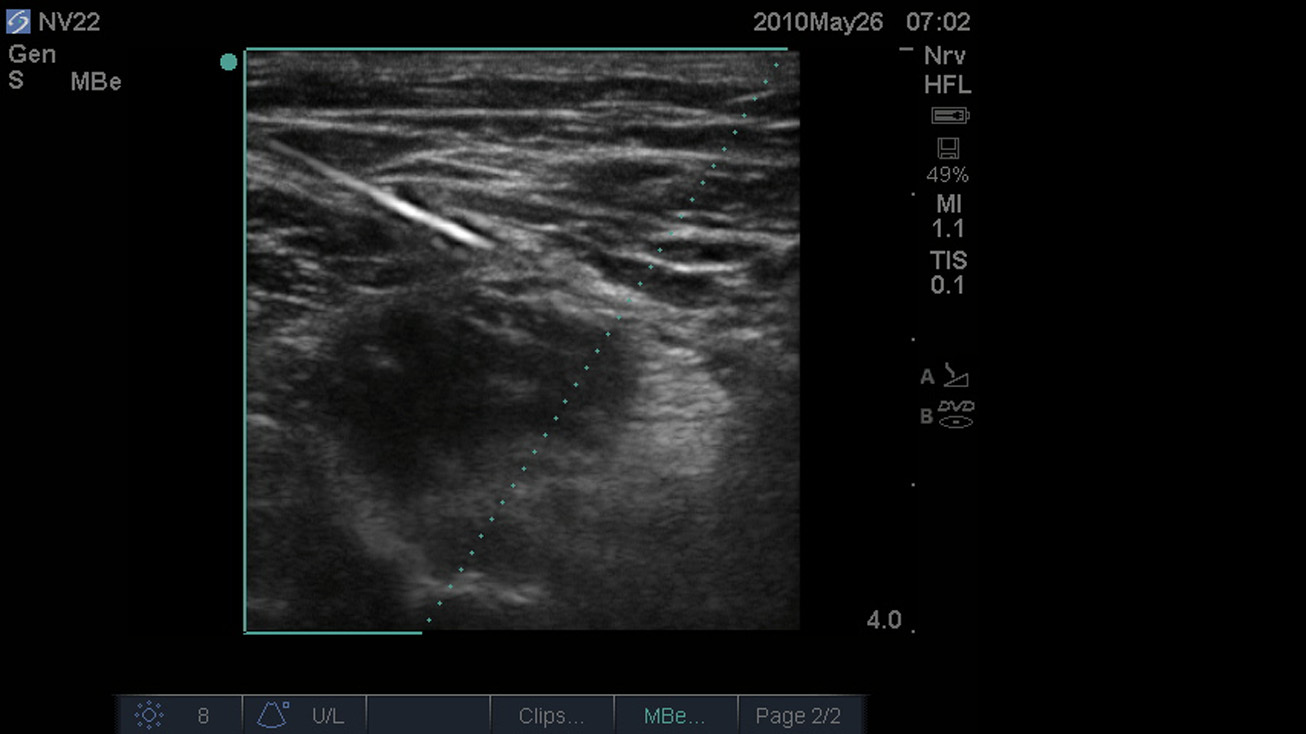

Bild: SonoMBe ein - steil, Nervus femoralis, 4 cm